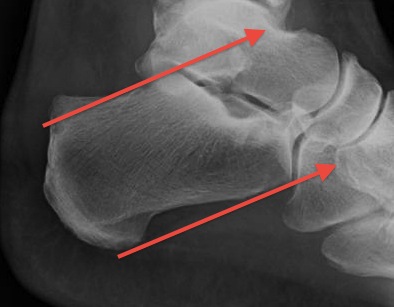

X-ray

Insertional achilles tendon spurs

- also present in asymptomatic patients

Calcification of bone-tendon interface with spur

Haglund's Deformity

- bony protuberance of posterosuperior calcaneus

Pavlov's parallel pitch lines

- lateral weight bearing x-ray

- draw parallel pitch lines

- defines Haglund's deformity to be removed (above second line)

Fowler's angle - Normal < 70° / Abnormal > 80°